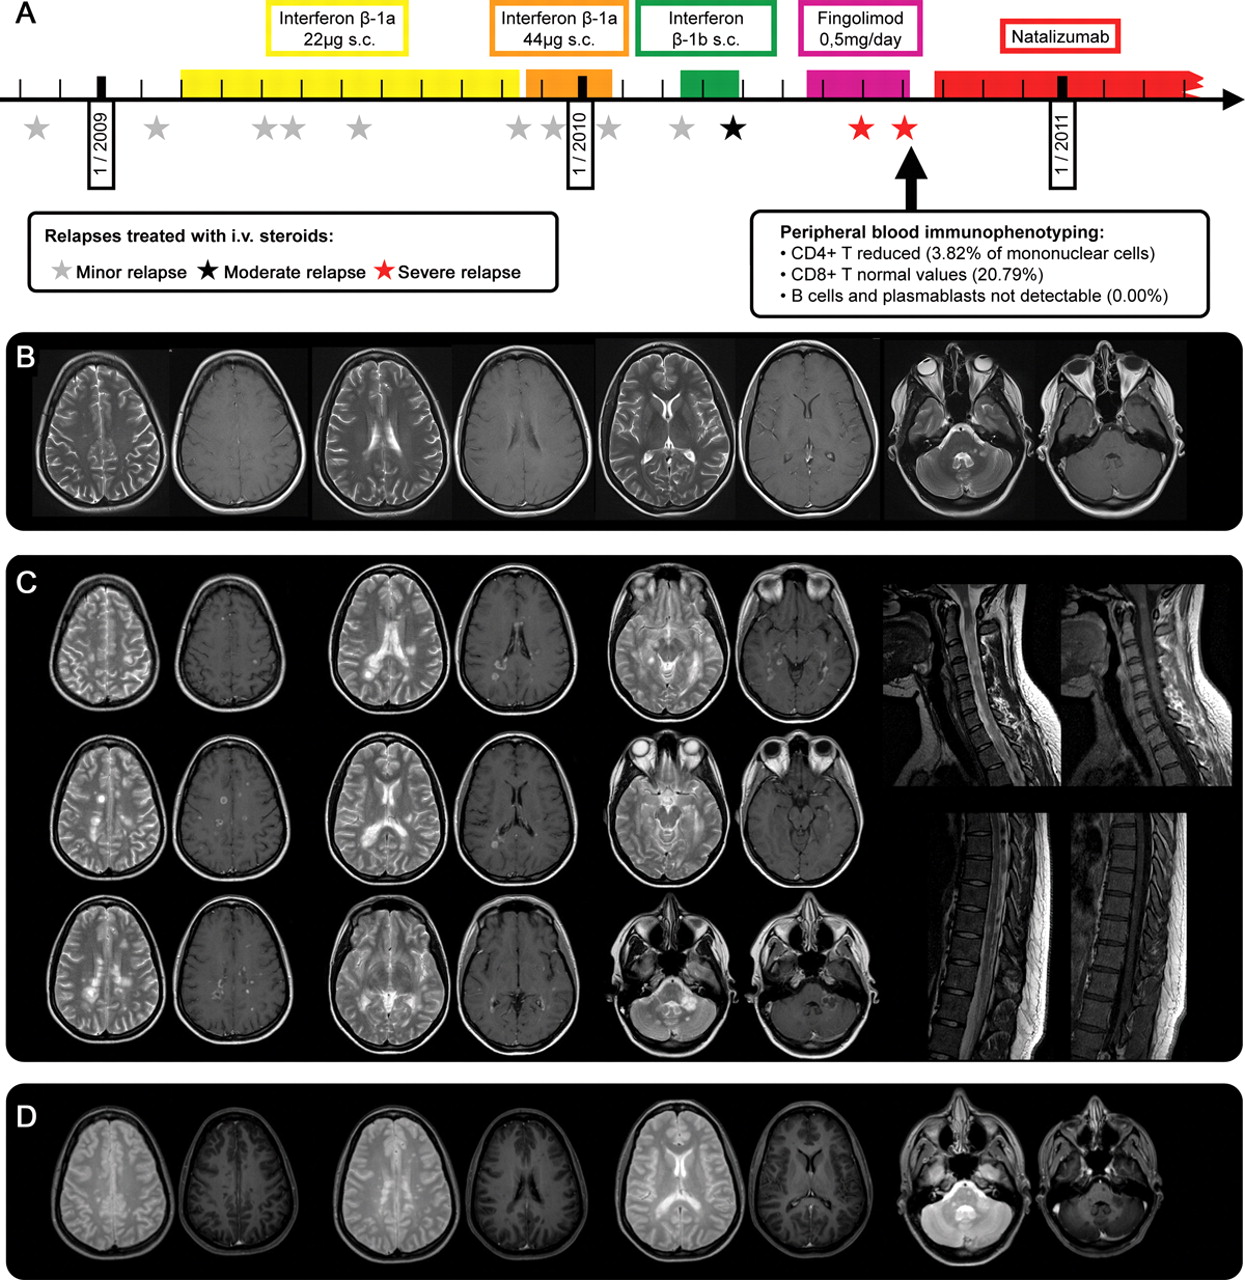

(A)病人的疾病过程:底部:血液immunophenotyping的结果。2010年(B) 5月3日,6周开始fingolimod疗法之前,大脑核磁共振(轴向T2和T1 + Gd)披露几幕上的和没有钆增强infratentorial多发性硬化病变。核磁共振成像是第四大剂量类固醇治疗后立即获得。(C) MRI在2010年9月入学。左:大脑核磁共振(轴向T2和T1 + Gd)披露29幕上的和infratentorial卵圆形病变以及汇合的活跃,一些与环状钆增强。此外,有一个大的病变在左侧小脑脚,没有扩散限制diffusion-weighted成像(没有显示)。右:颈椎和胸椎脊髓磁共振成像(矢状T2和T1 + Gd)显示几个活跃的病变。(D) MRI在2011年3月公布任何新的T2或Gd-enhancing脑损伤(脊髓成像没有显示)。

病人继续有波动的赤字主要归因于努力和Uhthoff现象。然而,治疗开始后的6周她开发了一个严重的复发(eds 4.0),大剂量静脉注射类固醇后,只是略有提高。

当病人被我们医院9月8日,2010年,剩余共济失调已经恶化后最后一周内第二次严重的复发。她面对严重的步态和肢体共济失调,眼球运动的赤字,轻微的面部麻痹,轻微tetraparesis锥体束的迹象,双方感觉赤字,和泌尿功能障碍(eds 5.5)。因为核磁共振扫描(图C)导致颅内脓肿的怀疑,fingolimod前一天停止招生。

病人立即接受血浆置换疗法(9周期),表现出非凡的临床改善。在入院Natalizumab疗法开始2周。直到2011年9月,病人没有经历任何新的复发,和她的eds提高至2.5。核磁共振成像在3月和2011年8月以来没有透露任何新的损伤的起始natalizumab治疗(图D)。